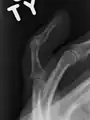

X-ray showing fracture at the insertion of the extensor tendon

The diagnosis is generally based on symptoms and supported by X-rays.[3] The injury can be accompanied by swelling and ecchymosis.[4]